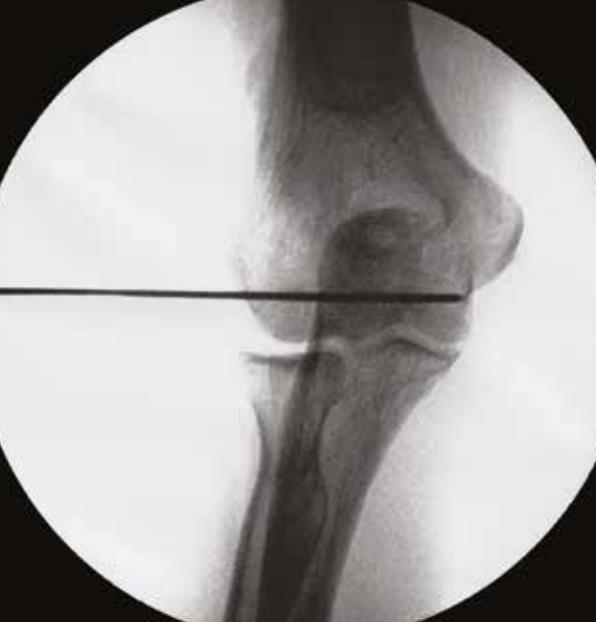

• Guide wire insertion

• advance the Guide-Wire (1.5mm K-wire) through the K-wire Guide and into the humerus, stopping short of the medial cortex

• caution

• DO NOT violate the medial cortex as it may result in ulnar nerve injury

• Fluoroscopic confirmation

• confirm that the Guide Wire (1.5mm K-wire) has been inserted to the correct depth and that the axis of rotation has been properly established using fluoroscopy